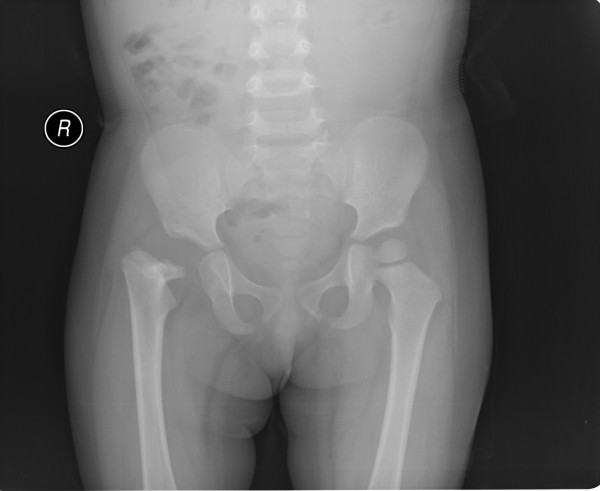

以下是引用jinguoji在2008-6-30 14:57:00的发言:[br]支持右股骨颈坏死伴髋关节脱位。

以下是引用jiangjing在2008-6-30 17:13:00的发言:[br]股骨头骨骺缺血性坏死,伴脱位

以下是引用wjyd在2008-7-2 14:41:00的发言:[br]股骨头坏死移位伴髋关节脱位